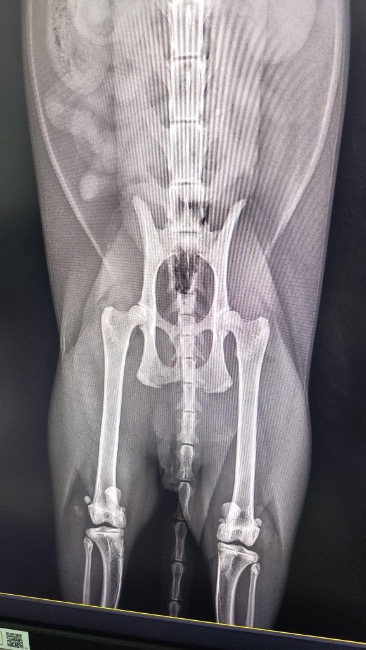

Zdiagnozowano u niego ciężką niestabilność obu rzepek, która sprawia, że każdy krok jest niepewny i bolesny. Dodatkowo lewa tylna kończyna wymaga specjalistycznego zabiegu TGR — wszczepienia protezy bloczka kości udowej.

To bardzo skomplikowana i kosztowna operacja, ale jedyna szansa, by Tymianek mógł normalnie chodzić i żyć bez cierpienia.

❗ Bez operacji jego stan będzie się tylko pogarszał!

Ból będzie narastał, pojawią się zwyrodnienia, a Tymianek — choć jeszcze taki młody — może zostać skazany na trwałe kalectwo. Już teraz widać, że ogranicza ruch, bo po prostu się boi.